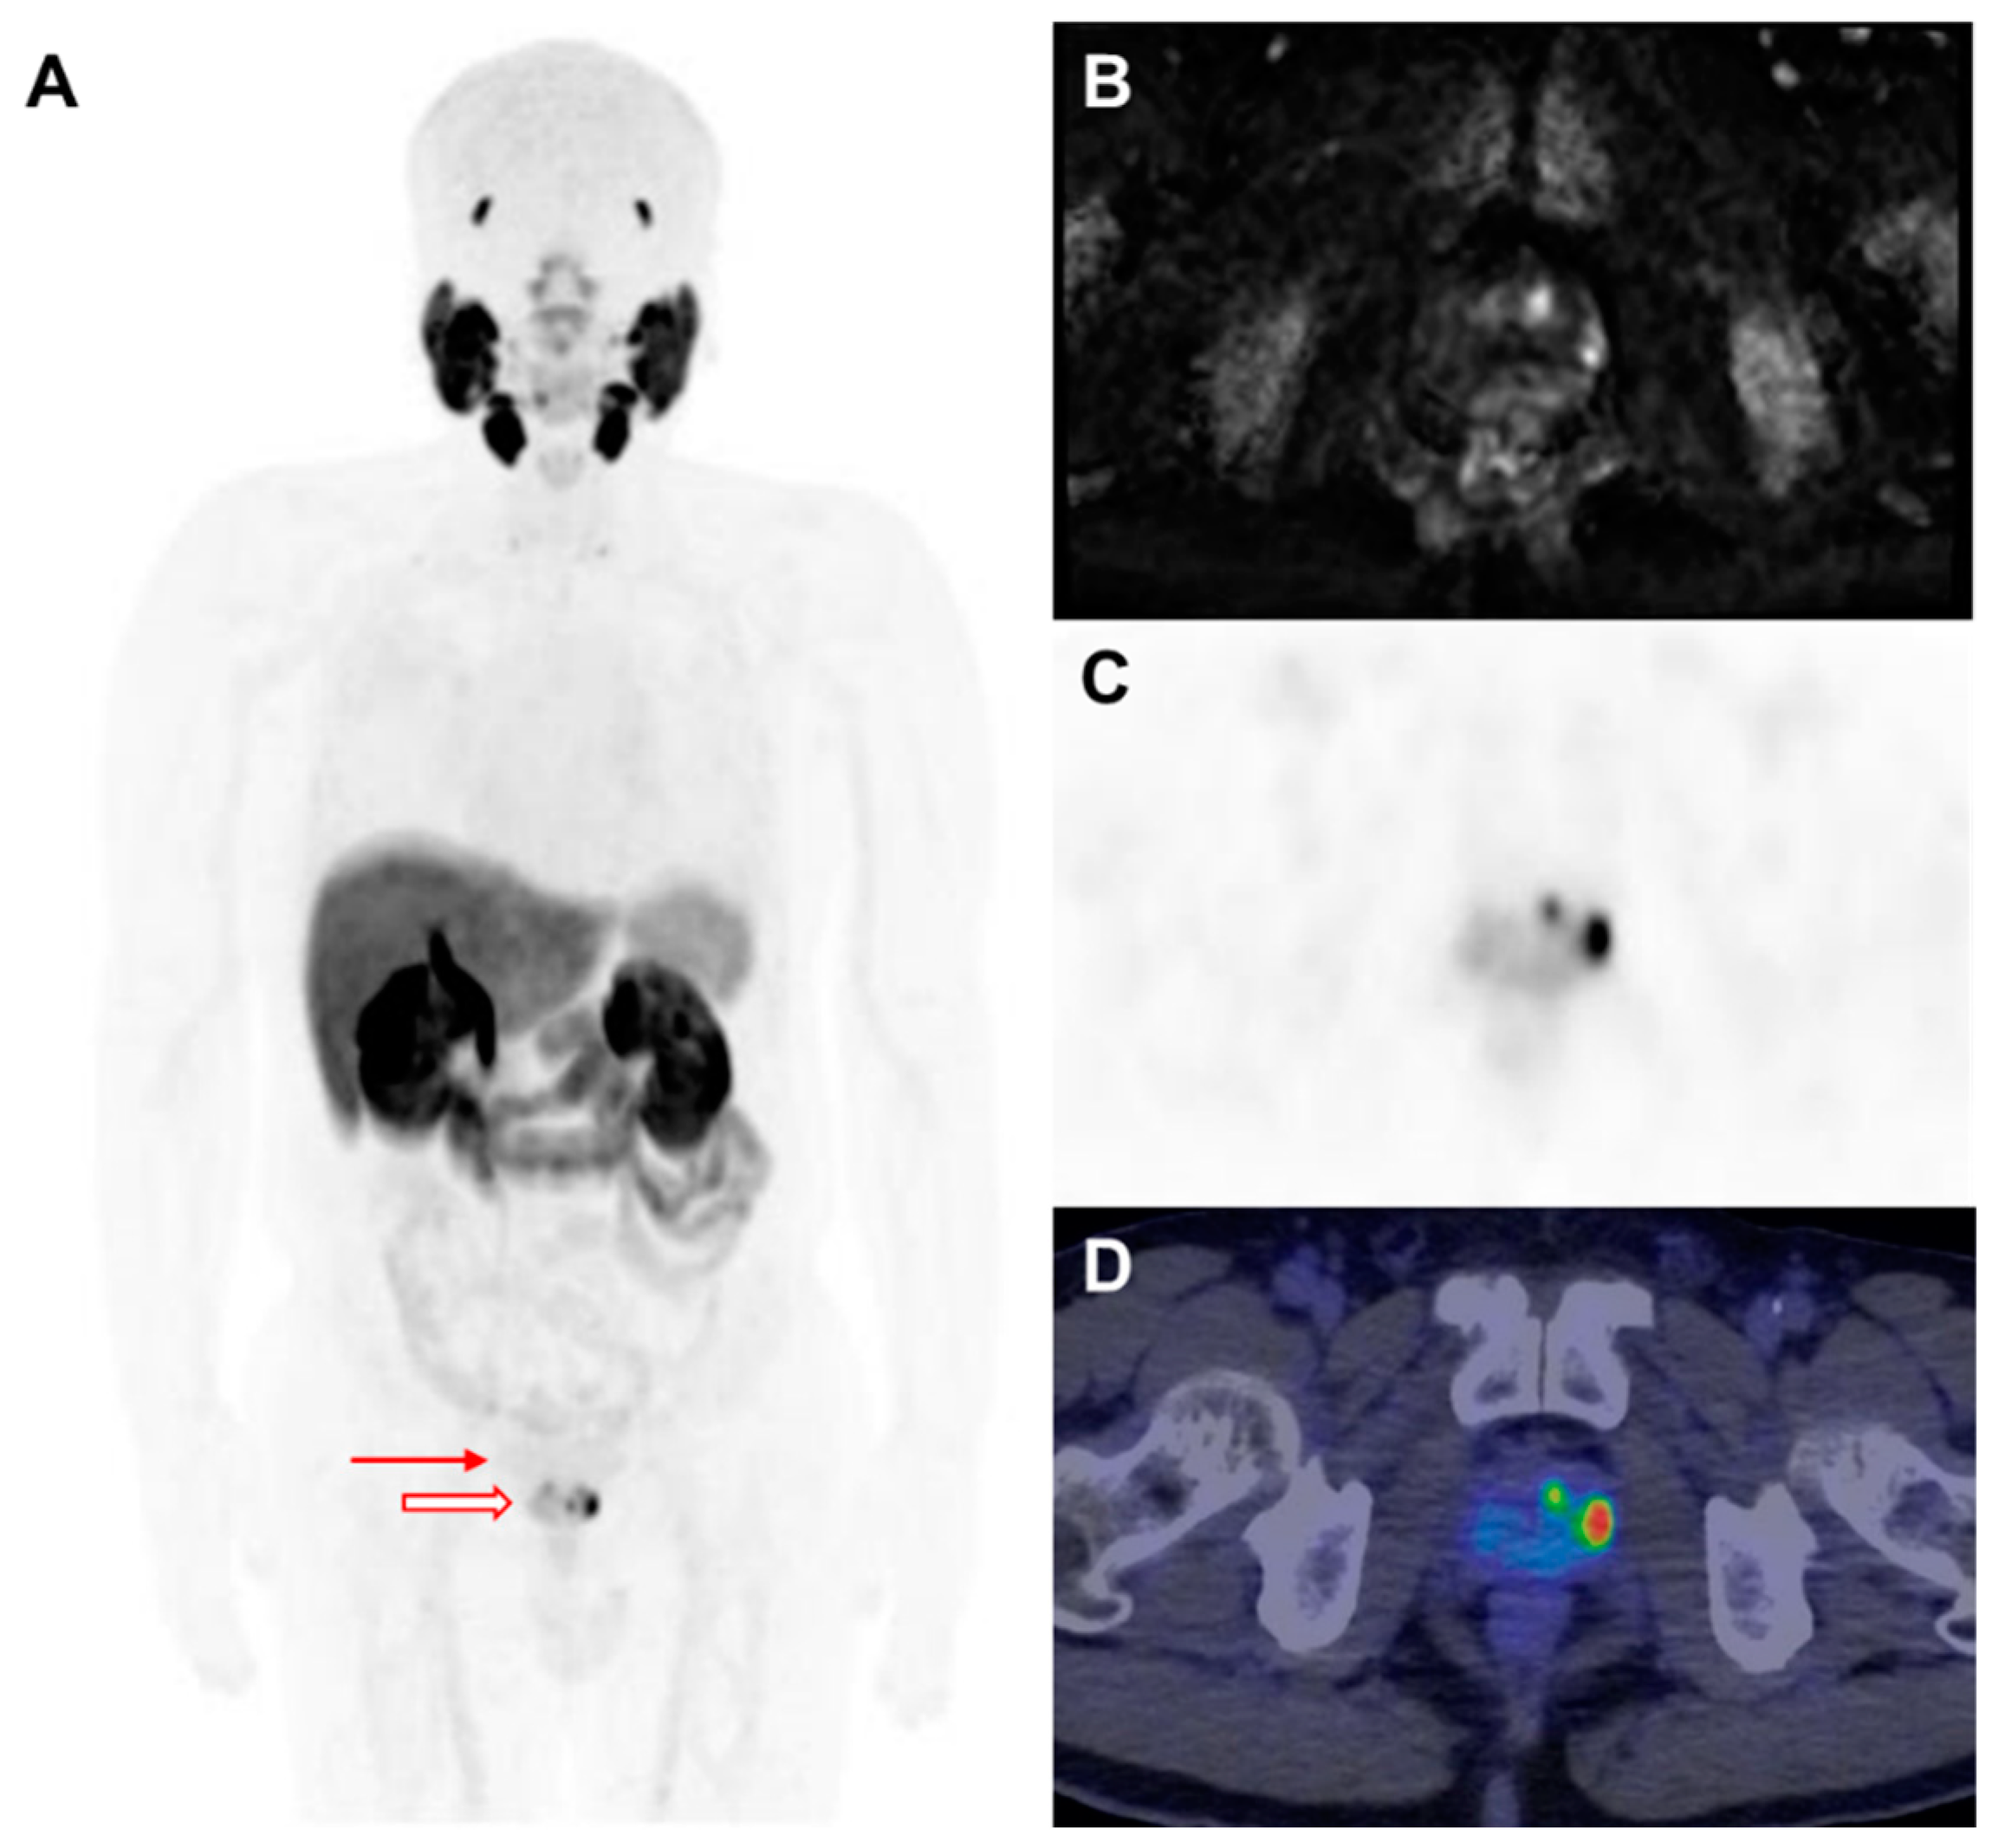

Figure 3.

A 70-year-old man with a history of benign prostatic hyperplasia was referred to the urology department for lower urinary tract symptoms and had an initial serum prostate-specific antigen (PSA) level of 3.4 ng/mL. A transrectal ultrasound (TRUS)-guided biopsy confirmed adenocarcinoma with a Gleason score of 5 + 5 = 10. Immunohistochemical analysis showed a loss of high-molecular-weight cytokeratin (HMW CK) and p63, with positive expression of alpha-methylacyl-CoA racemase (AMACR). (A) Maximum intensity projection images of F-18 PSMA PET demonstrated a strong uptake in the primary tumor without distant metastases. A low bladder activity (arrow) improved the visualization of the pelvic tumor (empty arrow). (B) T2-weighted magnetic resonance imaging revealed hyperintense areas in the left superior and lateral prostate, corresponding to the TRUS biopsy sites. (C) F-18 PSMA PET and (D) PET/CT fusion imaging confirmed focal PSMA uptake in these regions, aligning with the MRI findings and biopsy-confirmed tumor locations.